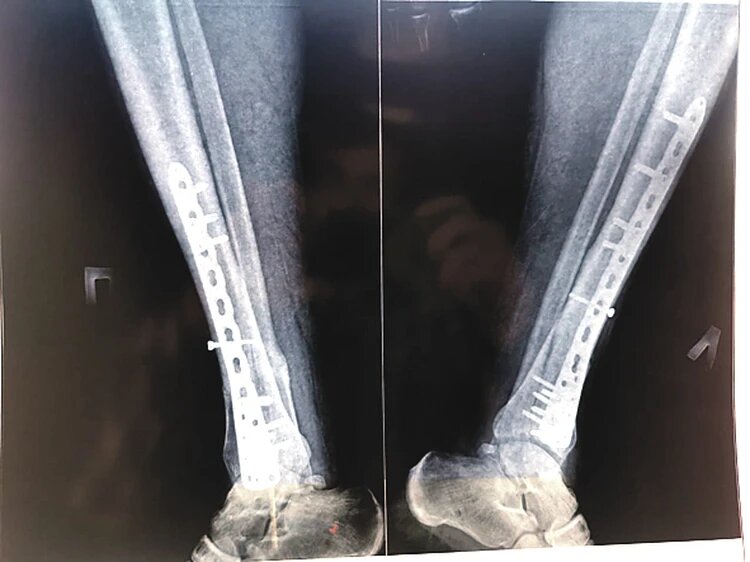

При падении Михаил Казаков сломал обе ноги и раздробил кости.

Всё рухнуло в один миг. В 2020 году, пытаясь сделать эффектный кадр на пожарной лестнице, актер сорвался с 12-метровой высоты. Результатом погони за красивым селфи стали раздробленные ноги и страшный вердикт врачей, который разделил его жизнь на «до» и «после». Он стал инвалидом.